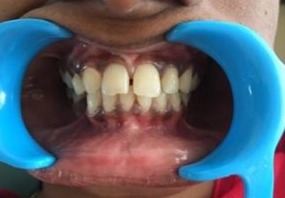

PRE - OP POST - OP